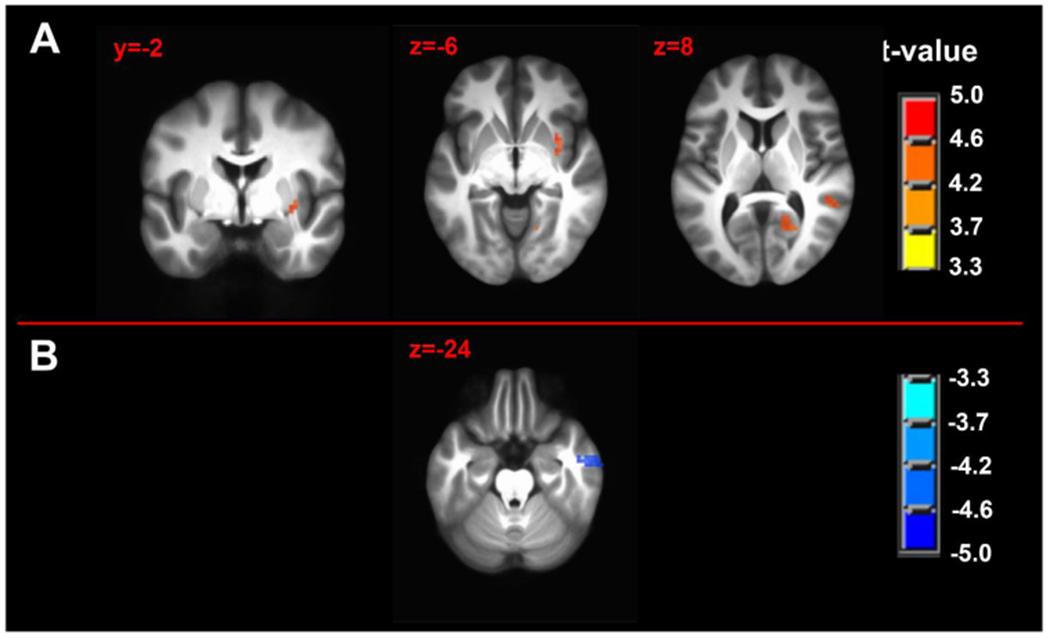

Of all hypothesized FC dyads, only PAG and subgenual ACC was weakly altered during pain (F = 3.34; p = 0.074; pain-free>pain d = 0.25). After pain induction sACC-PAG FC became positively correlated with pain intensity (R = 0.38; t = 2.81; p = 0.007). Right PBN-PAG FC during pain-free rest positively correlated with subsequently experienced pain (R = 0.44; t = 3.43; p = 0.001). During pain, this connection's FC was diminished (paired t=-3.17; p = 0.0026). In whole-brain analyses, during pain-free rest, FC between left AMYG and right superior parietal lobule and caudate nucleus were positively correlated with subsequent pain. During pain, FC between left AMYG and right inferior temporal gyrus negatively correlated with pain. Subsequent pain positively correlated with right AMYG FC with right claustrum; right primary visual cortex and right temporo-occipitoparietal junction CONCLUSION: We demonstrate sACC-PAG tonic pain FC positively correlates with experienced pain and resting right PBN-PAG FC correlates with subsequent pain and is diminished during tonic pain. Finally, we reveal PAG- and right AMYG-anchored networks which correlate with subsequently experienced pain intensity. Our findings suggest specific connectivity patterns within the DPMN at rest are associated with subsequently experienced pain and modulated by tonic pain. These nodes and their functional modulation may reveal new therapeutic targets for neuromodulation or biomarkers to guide interventions.

在所假设的所有 FC 二联体中,只有 PAG 和 subgenual ACC 在疼痛时发生微弱改变(F=3.34;p=0.074;无痛>疼痛 d=0.25)。在疼痛诱导后,sACC-PAG FC 与疼痛强度呈正相关(R=0.38;t=2.81;p=0.007)。右 PBN-PAG 在无痛休息时的 FC 与随后经历的疼痛呈正相关(R=0.44;t=3.43;p=0.001)。在疼痛期间,这种连接的 FC 减少(配对 t=-3.17;p=0.0026)。在全脑分析中,在无痛休息期间,左杏仁核和右顶叶上回和尾状核之间的 FC 与随后的疼痛呈正相关。在疼痛期间,左杏仁核和右颞下回之间的 FC 与疼痛呈负相关。随后的疼痛与右杏仁核与右屏状核、右初级视皮层和右颞枕顶叶联合区的 FC 呈正相关。